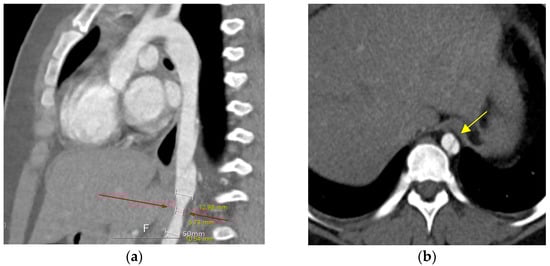

Ten years after the percutaneous PDA closure, limb blood pressure (BP) discrepancies were noted at the outpatient clinic (upper/extremity [U/E] 162/49 mmHg and lower/extremity [L/E] 131/100 mmHg). The patient was 11 years old, weighed 70 kg, and was 147 cm in height. The echocardiographic findings were as follows: closed PDA with mild aortic regurgitation and obstruction of the abdominal aorta with a Vmax of 2.5 m/s (maximum trans-stenotic pressure gradient of 27 mmHg). Left ventricular function was normal, with an ejection fraction of 64%. Chest radiography was nonspecific, and electrocardiography showed a normal sinus rhythm without specificity. Computed tomography (CT) further confirmed a dissecting descending aorta from T8 to T9 with complete luminal collapse and focal stenosis of the distal descending aorta at the T10 level. The diameter of the descending aorta was 12.9 mm in the upper portion, 5.7 mm in the stenotic portion, and 10.5 mm in the lower portion (Figure 1). Renal function test results remained within the normal ranges.

Figure 1. Aorta, abdominal CT. (a) Sagittal view, dissection of descending aorta. Focal stenosis at the distal descending aorta at the T10 level (red arrow). (b) Axial view, true lumen, and false lumen with intimal flap at T8–9 level (yellow arrow).